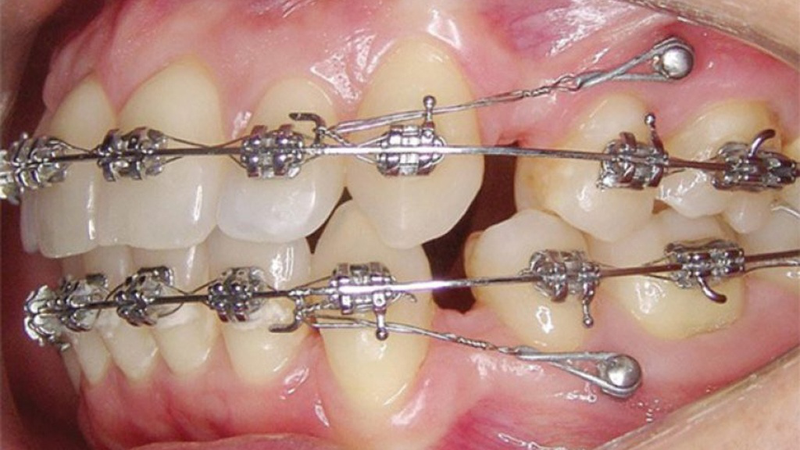

Orthodontic mini-screws are modern orthodontic tools — small titanium screws implanted into the jawbone to create a fixed anchor point. When placed correctly, they provide stable traction to help teeth move to the desired position. With a diameter of only 1.4mm to 2mm and a length of 6mm to 12mm, mini-screws are safe and biocompatible.

- Shorter treatment time: At Dental 365, the mini-screw placement procedure is quick and efficient, reducing total orthodontic time by 3–9 months. Our doctors assess your dental condition and recommend the best solution. Once implanted, the mini-screws guide your teeth into alignment with minimal discomfort.

- Increased precision in complex orthodontic cases: Thanks to their solid anchorage, orthodontic mini-screws allow precise control of traction force, ensuring accurate tooth movement and minimizing deviations — all while shortening your treatment journey.